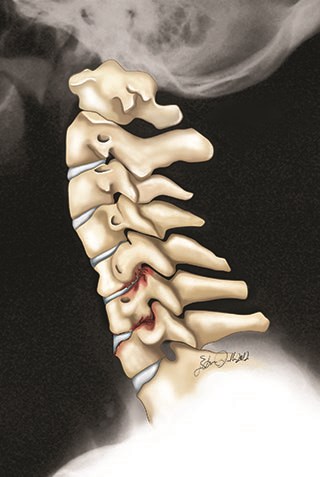

Boyun kemikleri arasında yastıklama ve şok emilimi görevlerini üstlenen diskler bulunmaktadır. Zorlanmalar, kazalar ve yaşlanmanın bir parçası olarak diskte meydana gelen bozulmalar sonucu içerisindeki jel kıvamlı sıvının dışarı çıkması, omurilik ve sinirlere baskı yapması ile oluşan klinik tablo boyun fıtığı olarak adlandırılır.

Servikal disk herniasyonu sonucu, çıkmakta olan sinir kökü tahrişi veya sıkışıklığın da servikal radikülopati gelişebilir. Genellikle boynunuzdaki fıtıklaşmış bir disk, disk alanı yüksekliği kaybı ve diskin kendisinin ilişkili periferal şişmesi dahil olmak üzere, servikal omurganın ilerleyici dejeneratif değişikliklerinin bir sonucu olarak gelişir.

Radikülopatinin semptomları arasında, kol ağrısı veya uyuşma ve bazen de boyun ağrısı ile ilişkili veya boyuna yayılan zayıflama yer alır. Boyun fıtığı klasik olarak kola yayılan ağrısıyı içerir. Bazen hasta belirli bir sinir kökü boyunca dolaşan acıyı tanımlar, ancak çoğu zaman şikayet, boyun bölgesinde ortaya çıkan ve koldan aşağıya doğru yayılan yaygın ağrıdır. Bir hasta, zaman zaman, semptomların başlangıcını, incitici bir travma veya yaralanma ile tanımlayabilir, ancak daha sık olmamakla birlikte, belirli bir olay tanımlanmaz.

Fizik muayenede refleks kaybı, kas zayıflığı veya atrofi ve belirli bir sinir kökü dağılımını izleyen ağrı veya uyuşma ararız. Sekiz servikal sinir kökü vardır. En çok etkilenen sinir kökleri C5, C6 ve C7’dir. Omurilik ya da ağrı üreten sinir kökleri üzerindeki baskıdır. Hastaların% 85’inden fazlasında, akut servikal radikülopati semptomları konservatifyani tedavilerimiz ile iyileşir.

Bir disk, bir defada çok fazla basınç uygulandığında bir disk aniden yırtılabilir veya zaman içinde tekrarlanan yaralanmalardan dolayı anulusun zayıflaması nedeniyle küçük bir kuvvet miktarından da kopabilir.